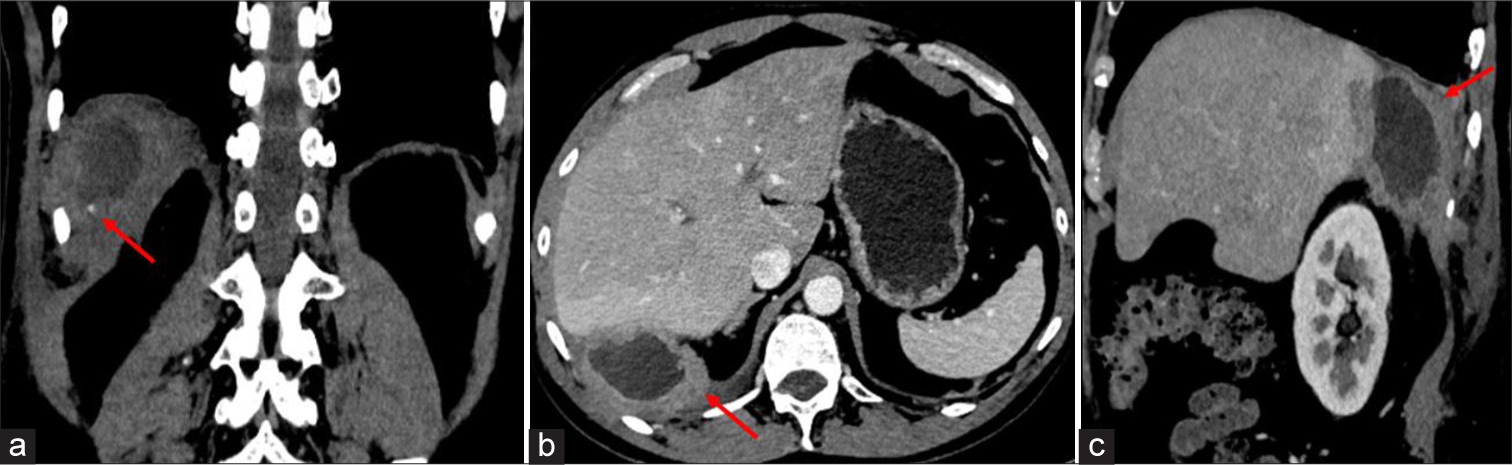

A 60-year-old male patient who had undergone a laparoscopic cholecystectomy 3 years ago for calculus cholecystitis presented with complaints of frequent right hypochondriac pain and fever. Ultrasound (USG) abdomen revealed a thick-walled collection in the subdiaphragmatic region near segment VI of the liver [Figure 1]. The patient had a similar history in the past for which an ultrasound guided aspiration was performed. A contrast-enhanced computed tomography (CECT) abdomen was advised in view of recurrent subdiaphragmatic abscess, which revealed a well-defined thick-walled peripherally enhancing hypodense collection in the right subdiaphragmatic region in contact with hepatic parenchyma of segment VI, with few tiny (2–3 mm) radiopaque foci noted in the wall of the collection [Figure 2]. Hence, based on imaging features, the possibility of dropped gallstones with recurrent abscess formation was considered. Laparoscopic-assisted abscess drainage with the extraction of retained gallstones was performed [Figure 3].

- (a) Computed tomography of abdomen plain (coronal view) showing an ill defined hypodense collection in right subdiaphragmatic region with thick wall and small calcific foci in the wall, (red arrow) indicates small calcific foci. (b) Contrast enhanced computed tomography of abdomen axial section showing central non enhancing hypodense collection with thick irregular peripherally enhancing wall. Red arrow indicating abscess in right subdiaphragmatic region. (c) Contrast enhanced computed tomography of abdomen axial section showing central non enhancing hypodense collection with thick irregular peripherally enhancing wall. Red arrow indicating abscess in right subdiaphragmatic region.